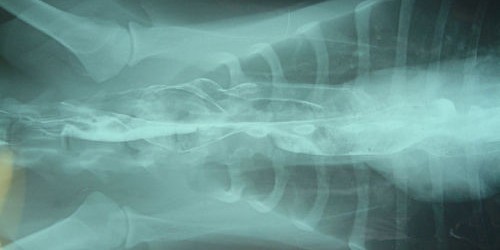

Thymectomy is a surgical removal of the thymus, a gland located in the mediastinum. In adult people this gland has no specific role and is practically inactive. However, it may be somehow associated with the onset of myasthenia gravis. This thesis has been proven in people who have been operated and whose symptoms have drastically improved once the gland has been removed from the body.